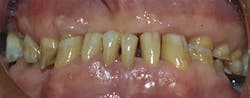

It is obvious to all dentists that a significant portion of their patients have worn their teeth so severely that they are nearly destroyed (figure 1).If you are treating such a patient, how could you possibly restore the occlusion without opening the VDO? When restoring patients with maxillary and mandibular complete dentures, how do you locate an appropriate VDO for their specific situation (figure 2)?

Figure 1: Worn teeth are a commonly observed condition in at least 30% of adult patients. When restoring the dentition with either crowns or removable dentures, opening vertical dimension of occlusion is usually indicated and sometimes mandatory.